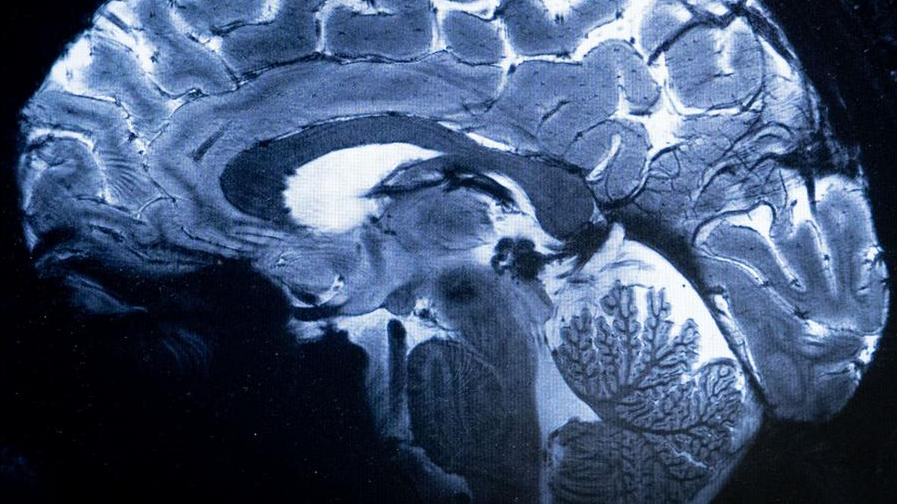

Los investigadores utilizaron imágenes de resonancia magnética de los cerebros de los participantes en el Framingham Heart Study, iniciado en 1948 en Framingham (Massachusetts), para analizar patrones de enfermedades cardiovasculares y de otro tipo.

Las resonancias magnéticas se realizaron entre 1999 y 2019 a participantes en el estudio Framingham nacidos entre las décadas de 1930 y 1970.

En el estudio cerebral participaron 3.226 personas (53 % mujeres y 47 % hombres) con una edad media de unos 57 años en el momento de la resonancia magnética.

La investigación, realizada por la Universidad de California Davis Health, comparó las resonancias magnéticas de personas nacidas en los años 30 con las de las nacidas en los 70, y descubrió aumentos graduales pero constantes en varias estructuras cerebrales. Por ejemplo, una medida que analiza el volumen del cerebro (volumen intracraneal) mostró aumentos constantes década tras década.

Para los participantes nacidos en la década de 1930, el volumen medio era de 1.234 mililitros, pero para los nacidos en la década de 1970, el volumen era de 1.321 mililitros, un aumento del 6,6 % en volumen.

La superficie cortical –una medida de la superficie del cerebro– experimentó un aumento aún mayor de una década a otra.

Según el estudio, los participantes nacidos en la década de 1970 tenían una superficie media de 2.104 centímetros cuadrados, frente a los 2.056 centímetros cuadrados de los participantes nacidos en la década de 1930, casi un 15 % más de volumen.